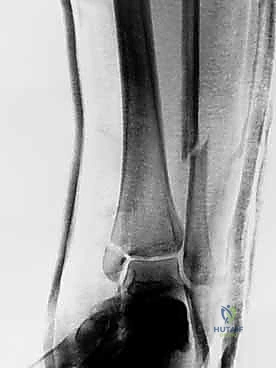

2. الأشعة السينية (X-rays)

هي الخطوة الأساسية. يتم أخذ صور بأوضاع مختلفة (أمامي، جانبي، ومائل - Mortise view) لتحديد مكان الكسر، درجة التفتت، ومدى تباعد العظام.